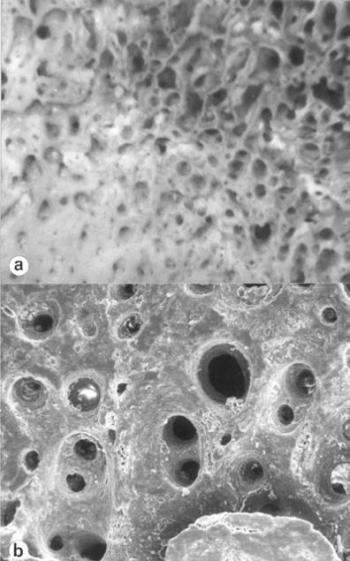

A poroticus hyperostosis (szinonimák: cribra orbitalia, cribra cranii, hyperostosis spongiosa, hyperostosis porotica, osteoporosis cranii) elsősorban a koponya, (főként a szemüreg) elváltozása (122. ábra) ám megjelenhet valamennyi lapos és csöves csonton. Mikroszkópos képével Hamperl és Weiss (1955), Marcsik és Kósa (1976), az elektronmikroszkópos és hisztomorfometriai eltérésekkel Józsa és Pap (1991) foglalkoztak. Morfológiai képe a folyamat súlyossága szerint eltérő. A poroticus típusban a corticalison tág nyílások keletkeznek (123. ábra), a spongiosus alakban a corticalis felszivódik, a felületet szívacsos állomány képezi (124. ábra), trabeculáris formában a diploe gerendái a környező csont szintje fölé burjánzanak (125. ábra) ami a rtg-felvételen „kefekoponya” alakjában jelentkezik (126. ábra). Mikroszkóposan a spongiosa gerendáinak feldúsulása, a gerendákon másodlagos üregek kialakulása állapítható meg (Józsa és Pap 1991), az egységnyi ürtartalomban megnő a csontvelőt hordozó felület, az újonnan képződő gerendák kóros szerkezetüek (123. ábra, 124. ábra, 125. ábra). Fokozott vörösvértest produkcióval járó valamennyi kórképben megjelenhet, vashiányos vérszegénységben 60-90%, Cooley anemiában 100%, sarlósejtes anaemiában 50-60%, maláriásokon 40-60%, cyanoticus szívfejlődési rendellenességekben 1-5% gyakoriságú (15. táblázat).

122. ábra. a) A homlokdudorokon és a szemüreg peremén (nyíl) elhelyezkedő cribrák. b) A kinagyított képen a corticalis felszívódása, a spongiosa felszínre türemkedése látszik. A széleken poroticus (csillag), a centrumban spongiosus területek. 10. századi gyermek. Sztereómikroszkópos felvétel 6× nagyítás